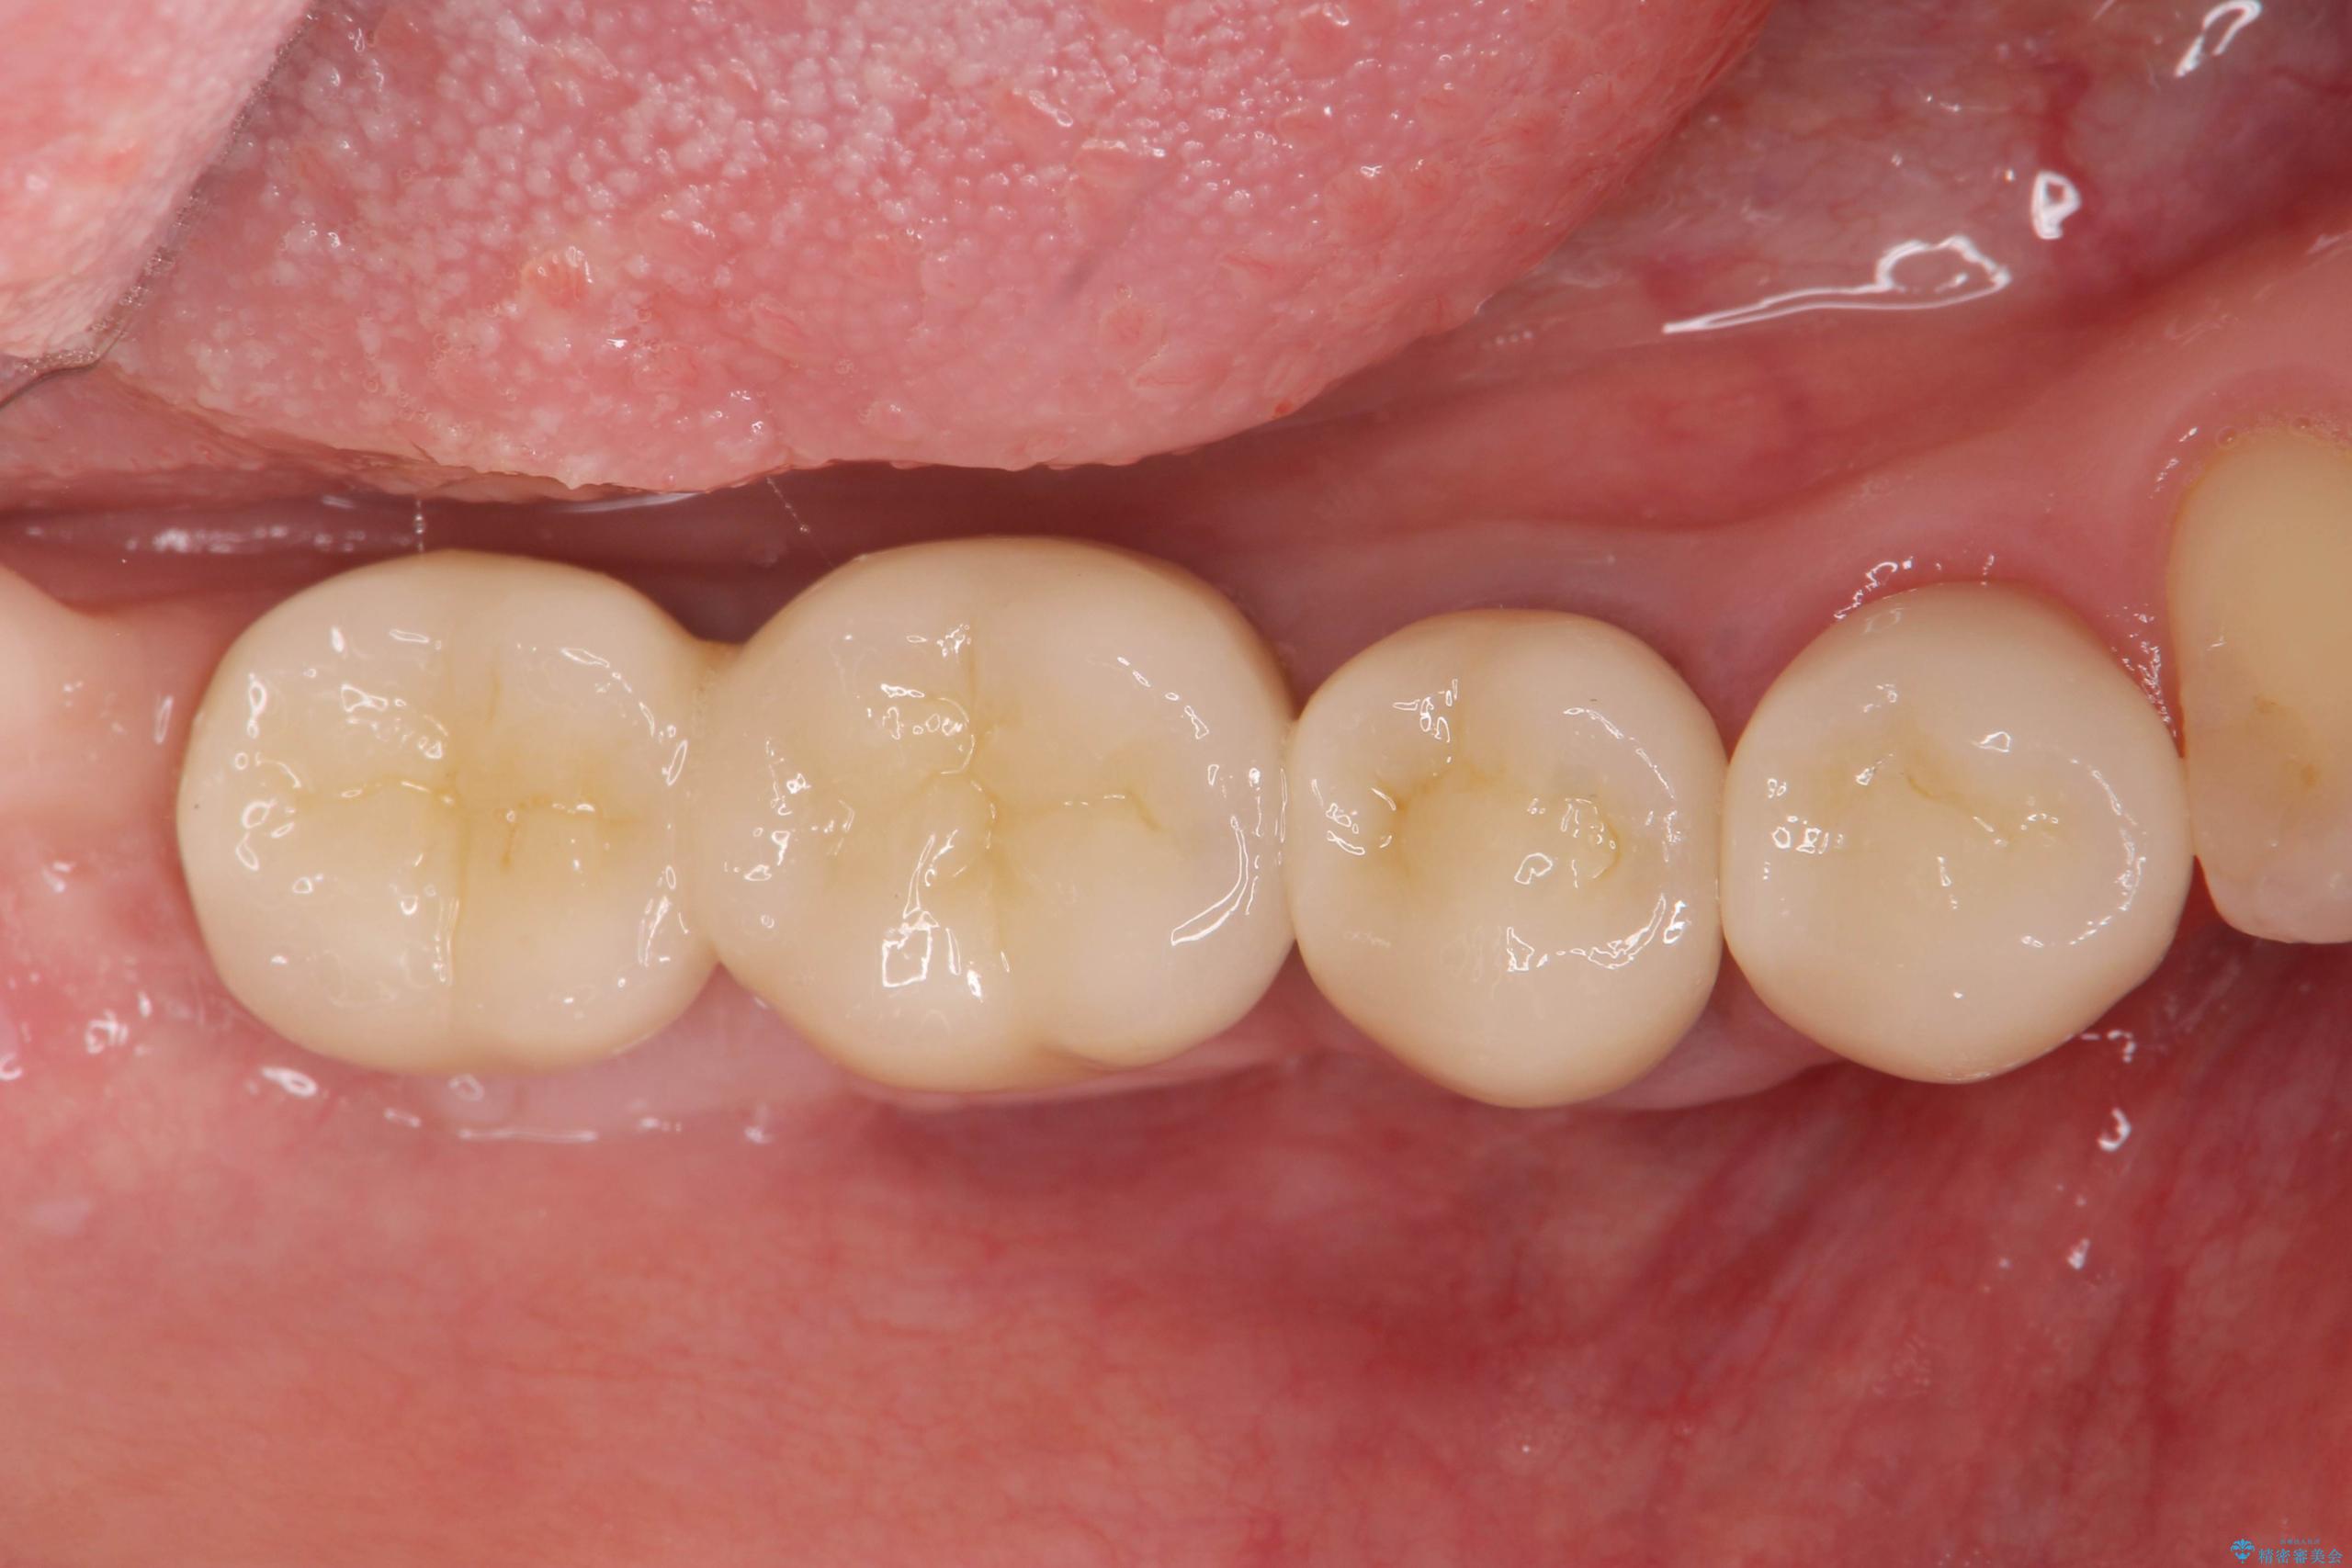

また、機能後のインプラント周囲の清掃性を高めるため遊離歯肉移植術を行っています。

インプラント周囲に強固な歯ぐきを移植することで、歯ブラシがしやすくなりインプラント周囲炎対策となります。